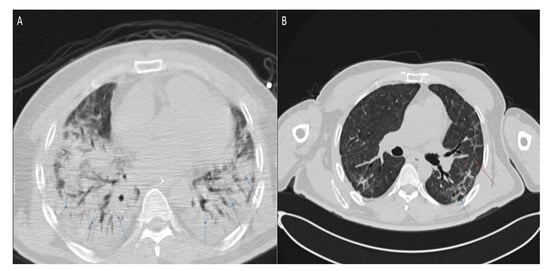

3.3. Lung Function Screening